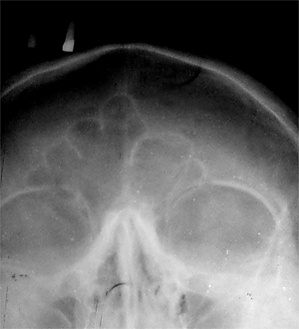

Ло́бная кость (лат. os frontale) — непарная кость мозгового отдела черепа; участвует в образовании переднего отдела свода черепа и передней черепной ямки его основания. Она состоит из четырёх частей: вертикально расположенной чешуи (лат. squama), двух горизонтальных глазничных частей (лат. pars orbitalis) и дугообразной носовой части (лат. pars nasalis)[1].

Лобная пазуха, sínus frontális, — парная воздухоносная полость, залегающая в передненижних отделах лобной кости между обеими её пластинками. Распространяясь назад, кверху и кнаружи, может иметь самые разные размеры. Лобные пазухи отделяются друг от друга вертикальной тонкой костной перегородкой, которая часто может быть отклонённой в ту или другую сторону; поэтому пазухи редко бывают одинаковыми. Лобные пазухи отсутствуют у новорождённых, обычно они развиваются к 7—8 годам, а максимального размера достигают уже после полового созревания. Размеры пазух резко варьируют, и обычно у мужчин они бывают больше чем у женщин. Пазухи выстланы слизистой оболочкой и сообщаются каждая со средним носовым ходом.